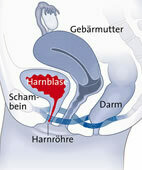

Ableitende Harnwege bei der Frau

© W&B/Szczesny

Unterer Harntrakt

Aus der Blase hinaus führt die Harnröhre (Urethra), die bei der Frau aus anatomischen Gründen wesentlich kürzer als beim Mann ist. Dies ist einer der Faktoren, die dazu führen, dass Frauen eher an Entzündungen der Harnwege leiden. Denn über die kurze Harnröhre können Keime leichter in die Blase gelangen und dort eine Blasenentzündung auslösen. Blase und Harnröhre gelten auch als unterer Harntrakt.